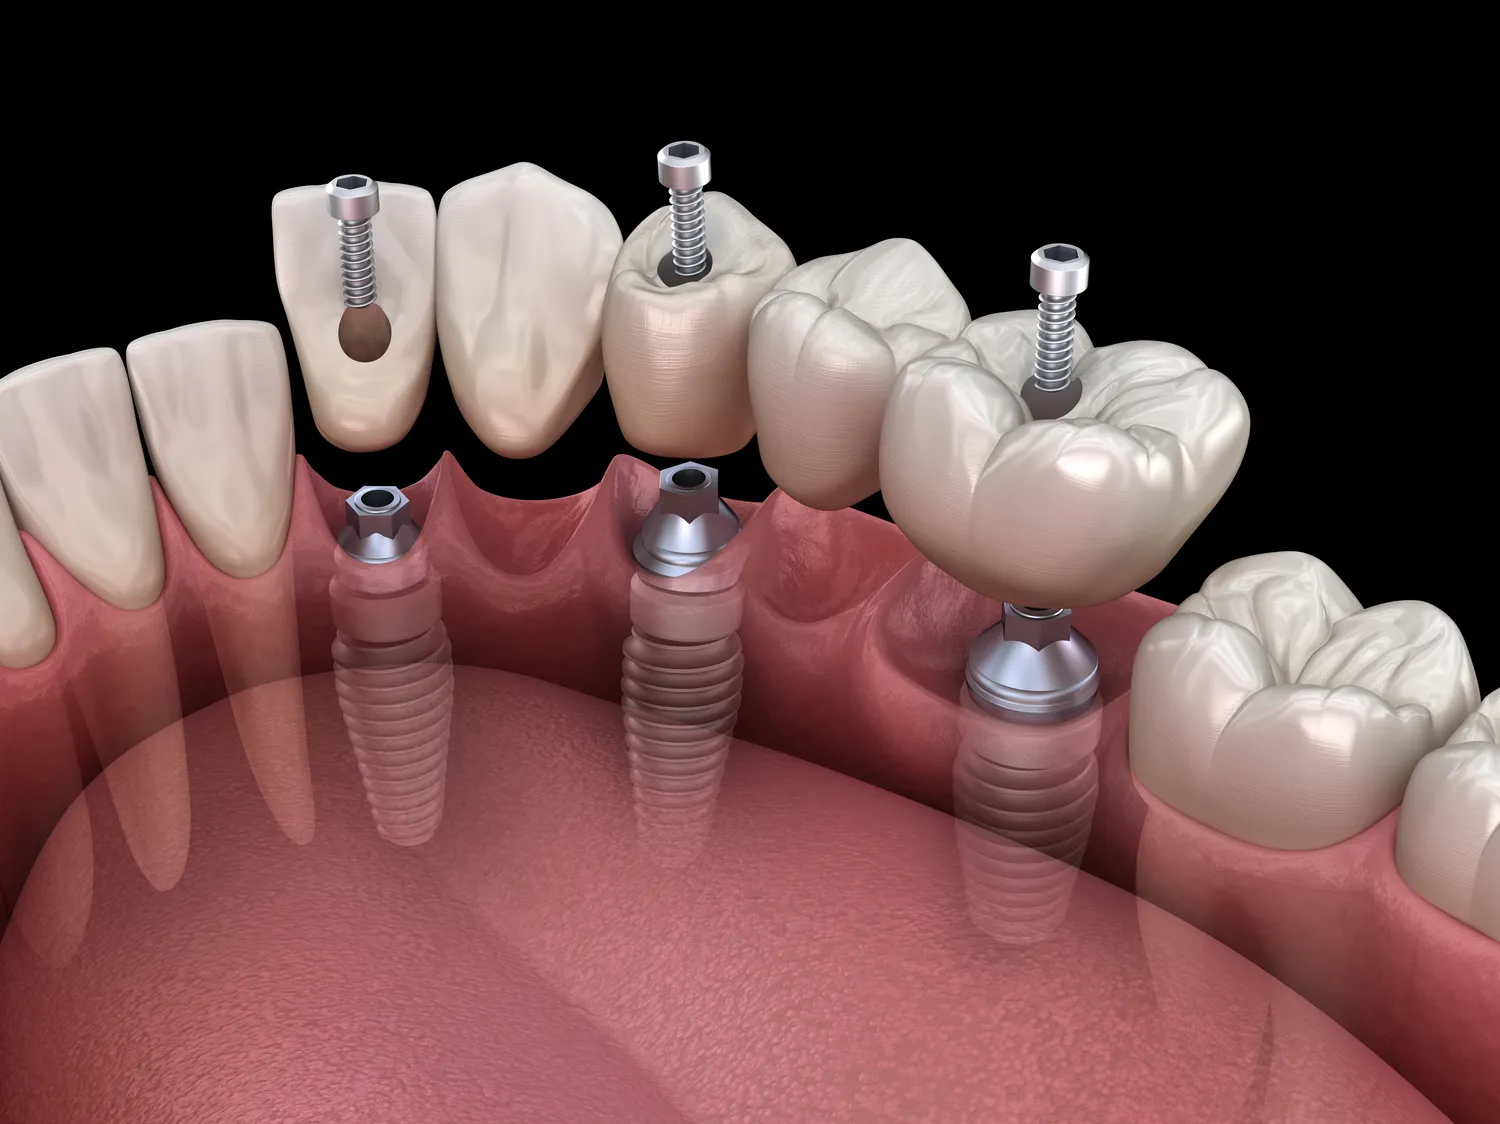

Jakie metody leczenia stosuje gabinet podologiczny w Koszalinie

Gabinet podologiczny w Koszalinie stosuje różnorodne metody leczenia schorzeń stóp, aby zapewnić pacjentom kompleksową opiekę. W przypadku grzybicy paznokci i skóry często wykorzystuje się terapie farmakologiczne oraz zabiegi laserowe, które skutecznie eliminują infekcje. Podolodzy mogą również zalecać stosowanie specjalistycznych preparatów do pielęgnacji stóp oraz wskazówki dotyczące higieny, aby zapobiec nawrotom choroby. W przypadku odcisków i modzeli najczęściej stosuje się zabiegi usuwania ich za pomocą narzędzi podologicznych oraz specjalnych preparatów keratolitycznych. Dla pacjentów z deformacjami stóp dostępne są różne metody korekcyjne, takie jak wkładki ortopedyczne czy ortezy, które pomagają w prawidłowym ułożeniu stopy i redukcji bólu. W gabinecie podologicznym w Koszalinie można także skorzystać z terapii manualnej oraz rehabilitacji, które mają na celu poprawę funkcji stóp oraz zmniejszenie dolegliwości bólowych.